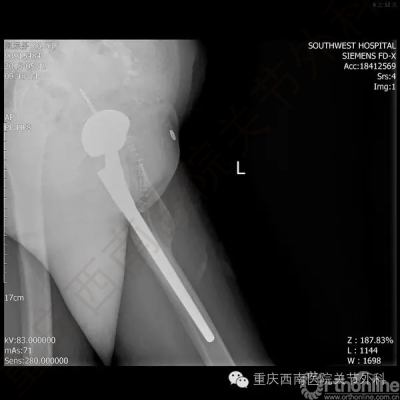

5月17日上午9:30,杨柳教授为赵女士实施了个体化导航器辅助下的全髋关节置换术。(图6)

手术耗时1小时50分钟,术中失血量100ml。术后第二天患者下地部分负重行走训练,5天患者康复出院。术后X片如图。